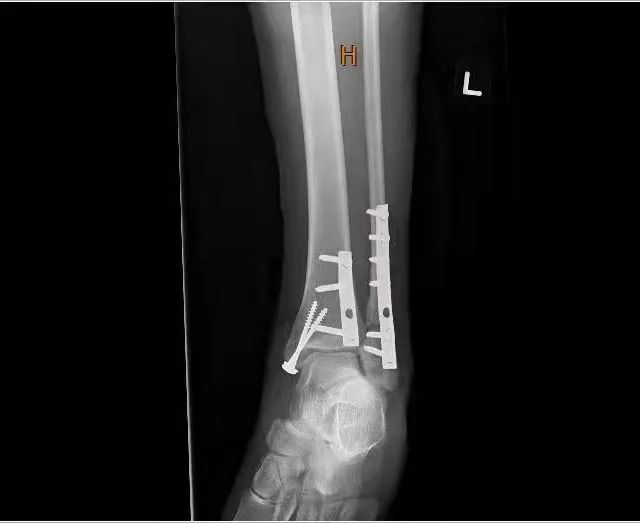

受伤三周后,我终于做了手术,醒来的时候,我已经在术后观察室了,医生在我脚踝的内外侧各放了一块钢板和几枚钢钉,还给我办了植入证明。

术后X光检查可见钢板和钉。

和很多骨折患者一样,我也穿上了特制的防护靴,穿上钢板,穿上“战斗靴”,我感觉自己就像一个现代版的钢铁侠。